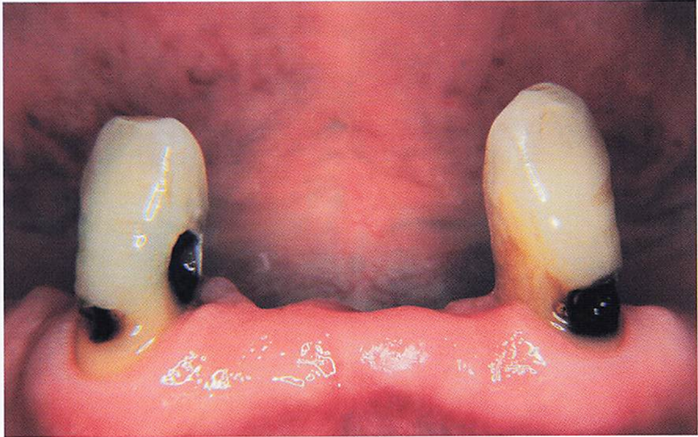

午後-39

54歳の女性。ブラッシング時に下顎左側中切歯に痛みを感じることを主訴として来院した。同歯の唇側歯頚部を探針で擦過すると一過性の痙痛を確認した。初診時の口腔内写真を別に示す。 露出根面に塗布するのはどれか。1つ選べ。